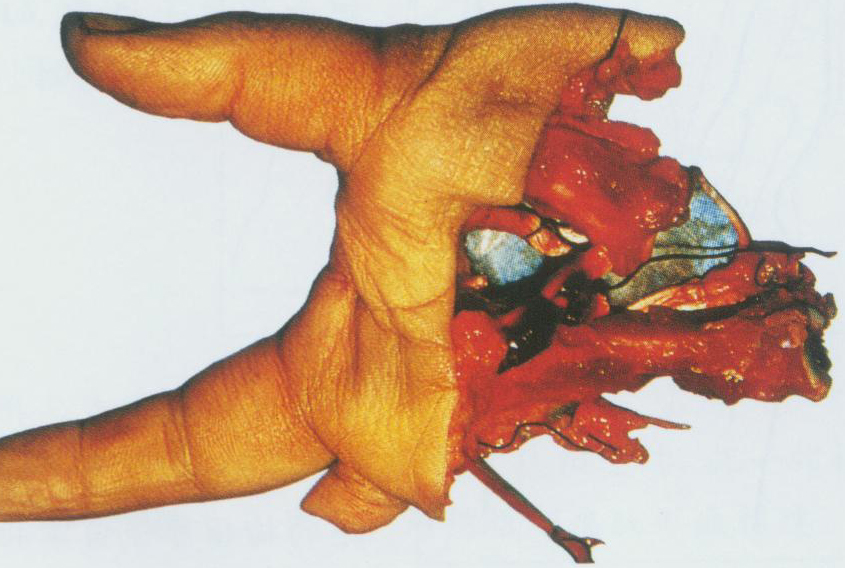

手术部位反复刺激 (SRSS) 是一种罕见的并发症,发生在手术后,当手术部位的组织受到持续性刺激时。症状

SRSS 的症状通常在手术后数周或数月内出现。这些症状可能包括:手术部位持续性疼痛或不适手术部位压痛或触痛手术部位皮肤的增厚或硬化手术部位的肿胀手术部位的异常感觉,如灼烧感或刺痛感

SRSS 的确切原因尚不清楚,但可能涉及以下因素:神经损伤: 手术可能会损伤手术部位的神经,导致异常的感觉。炎症: 手术部位的炎症可能会刺激神经。疤痕组织: 手术后的疤痕组织可能会压迫或拉扯神经。异物: 手术部位的异物,如缝线或手术器材,可能会刺激神经。